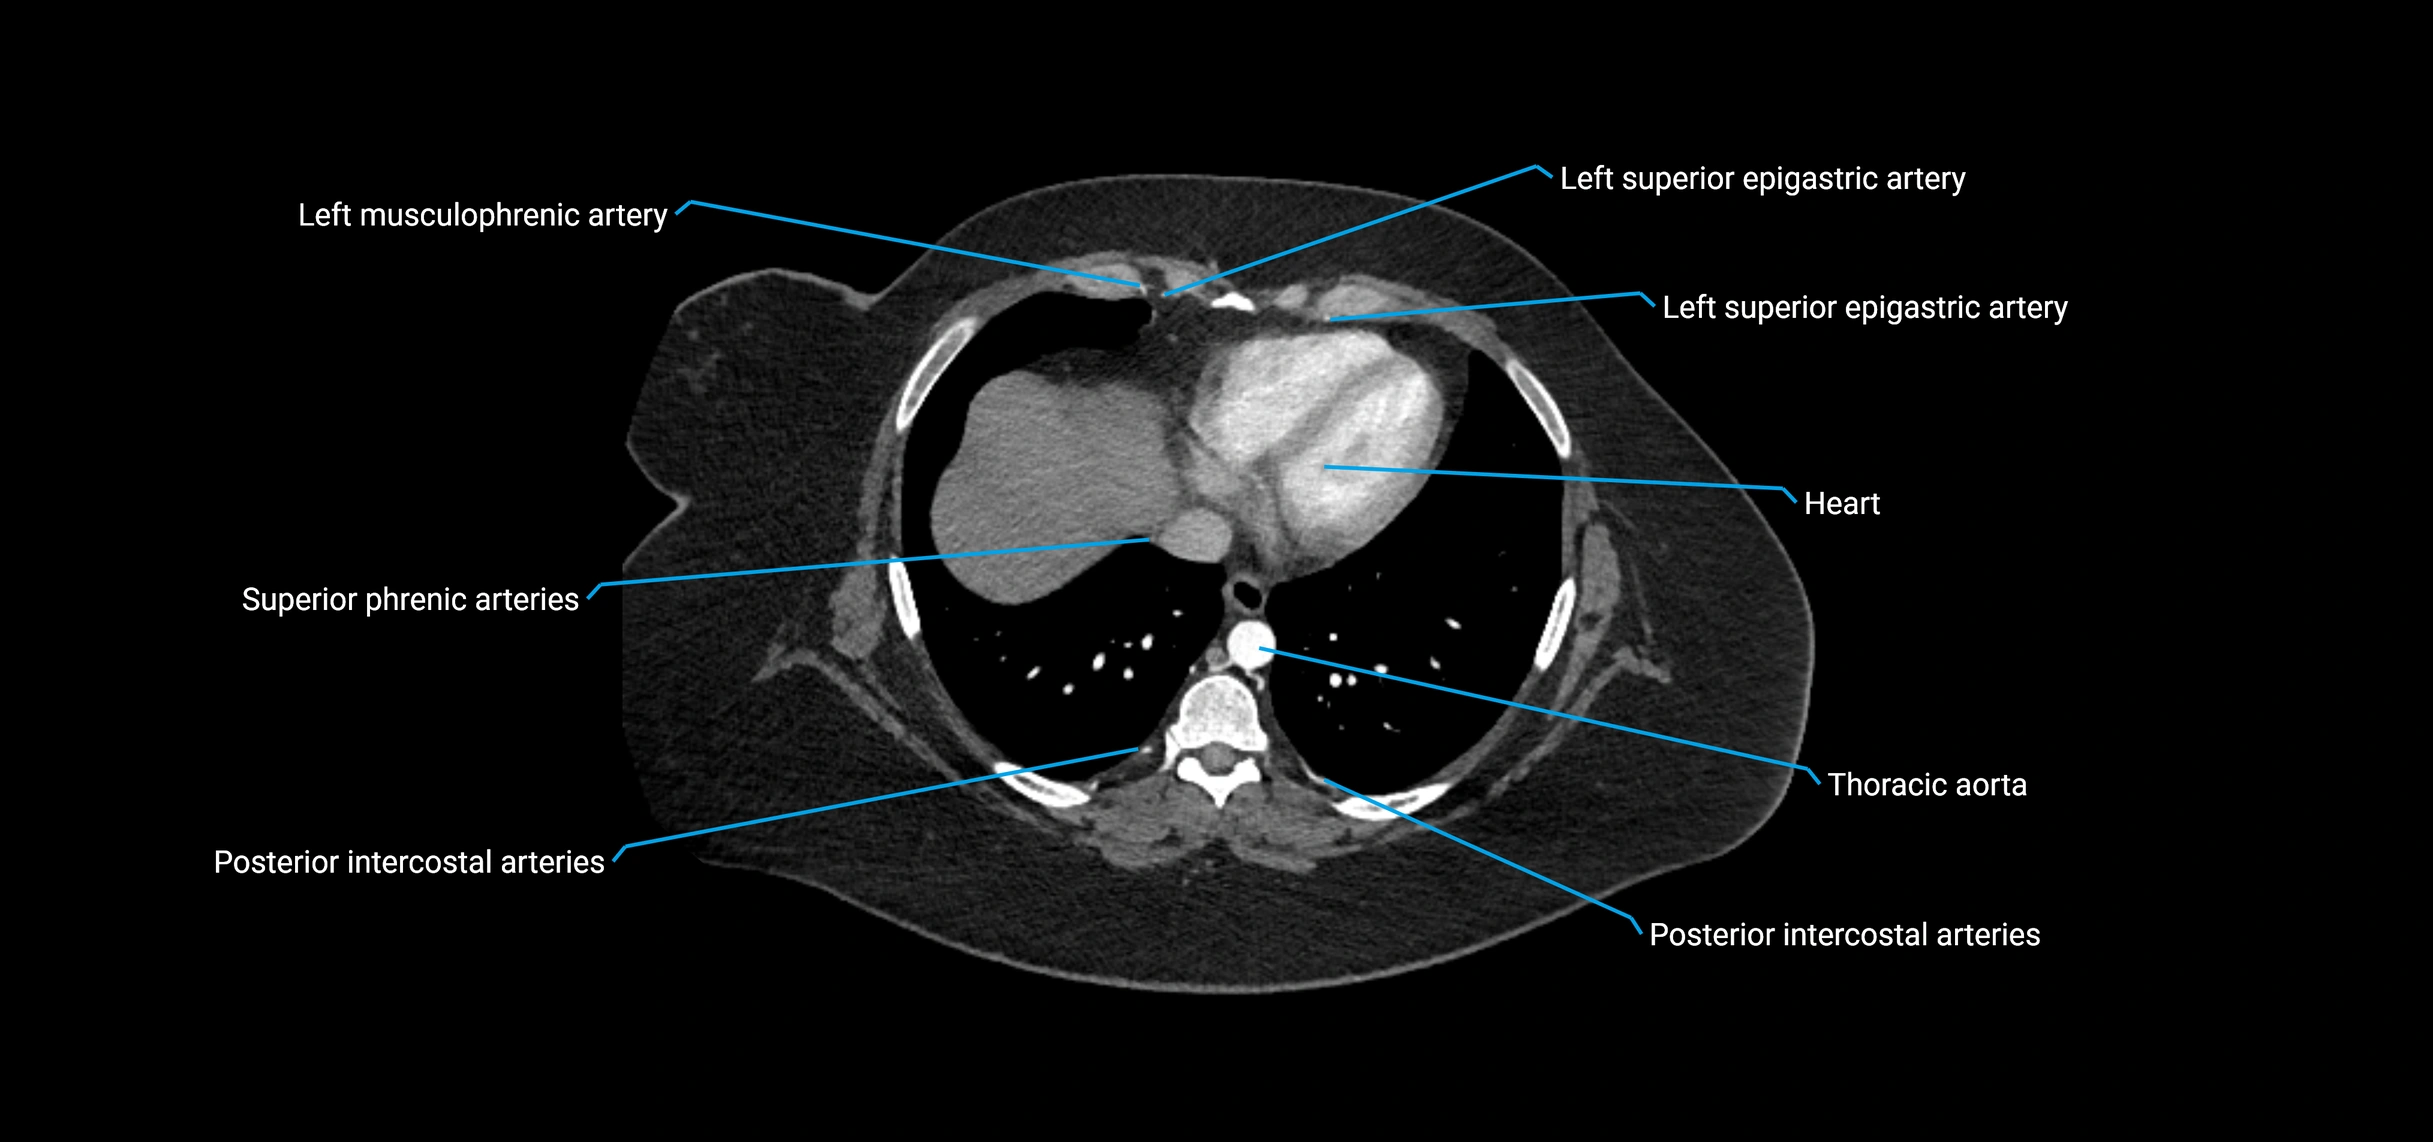

MRI images

image

MRI Appearance

T1-weighted images:

• Flowing blood appears as a signal void (black lumen)

• Vessel wall appears as a thin hypointense rim; retroperitoneal fat enhances contrast

T2-weighted images:

• Lumen remains a signal void due to flow

T1 Post-Contrast (Gadolinium-enhanced):

• Aortic lumen enhances brightly and homogeneously

• Clearly demonstrates aneurysm, stenosis, dissection, mural thrombus, or aortic wall enhancement in vasculitis

MRA (Magnetic Resonance Angiography):

• Contrast-enhanced MRA provides high-resolution imaging of the aorta and its branches

• Allows 3D reconstruction of visceral, parietal, and terminal branches

• Excellent for evaluating aneurysm size, dissection flap, stenosis, or preoperative planning